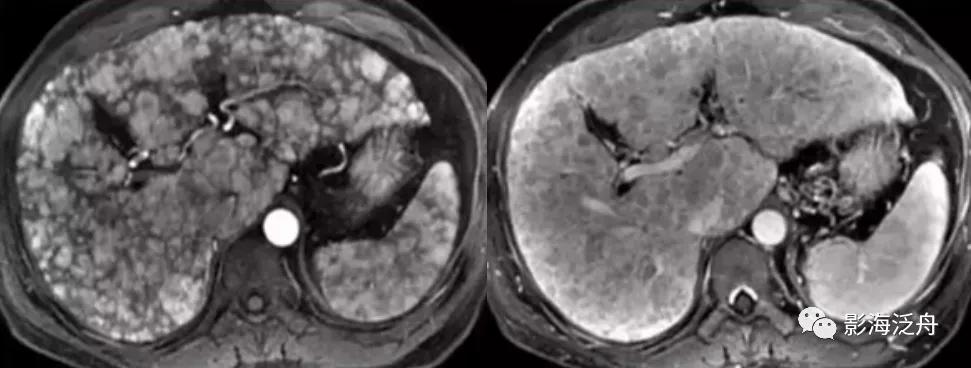

一例比较典型的肝硬化病例:T1WI上呈均匀稍高信号的再生结节(绿箭头)遍布全肝,再生结节在T2WI上呈明显低信号,这种低信号也是由于铁质沉积造成的,再生结节周围的纤维分隔因炎症浸润而呈高信号(红箭头)。

增强延时期,富纤维的肝组织呈较明显强化,而再生结节在纤维化背景肝实质的衬托下呈相对低信号(红箭标注几个较典型的再生结节)。

5.弥漫型肝癌

弥漫型肝癌,由无数个1cm以下的小结节遍布全肝,部分区域呈融合改变(看起来结节比较大),增强动脉期诸病灶呈明显强化,门脉期造影剂廓清,呈典型的“快进快出”强化。